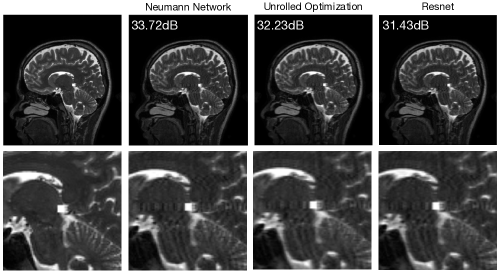

Recovering features not represented by training data.

The central assumption underlying all machine learning based image reconstruction methods is that the training data is representative of what we might see at test time. In some applications, such as medical imaging, it is unclear to what extent that assumption holds. One might imagine patients with unusual geometries in their anatomy or tumors that are not reflected by the training set [165, 166]. The ability of learned reconstruction methods to faithfully reconstruct such features remains poorly understood and can vary from method to method, as illustrated in Figure 12.